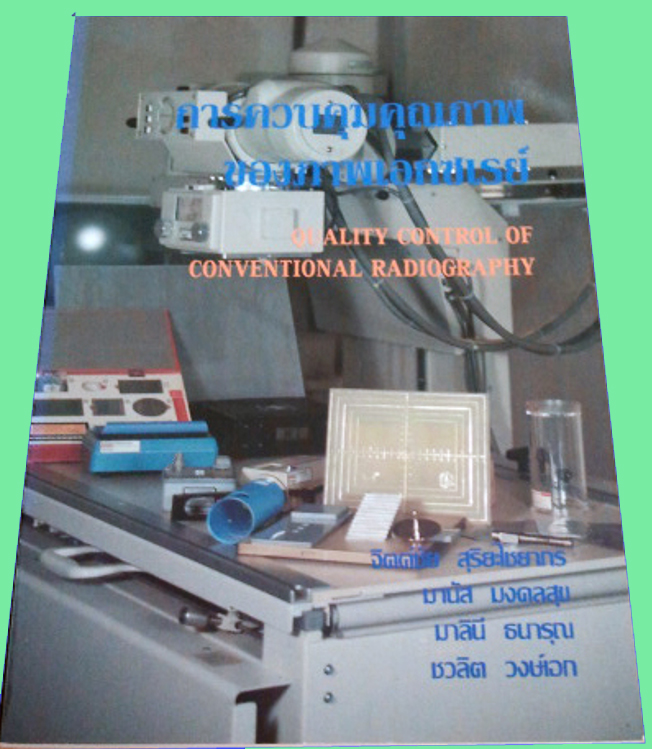

เช็กอาการ “หัวใจโต” ใครบ้างที่เสี่ยง ? – Chiang Mai News คู่มือการถ่ายภาพเอกซเรย์ เอกซเรย์ คู่มือ หนังสือ RT รังสีเทคนิค รังสี …

คู่มือการถ่ายภาพเอกซเรย์ เอกซเรย์ คู่มือ หนังสือ RT รังสีเทคนิค รังสี … การตรวจเอกซเรย์ปอด (Chest X-ray : CXR)

ประกายรังสี: QC เอกซเรย์จากแอนะล็อกสู่ดิจิทัล 10 ภาพเอกซเรย์แปลกๆ ที่คุณอาจจะยังไม่เคยเห็น

คุณภาพ ภาพเอกซเรย์ 2555 – GotoKnow รายการทดสอบ เครื่องเอกซเรย์วินิจฉัยทั่วไป และถ่ายภาพบนแผ่นเรืองแสง

คุณภาพ ภาพเอกซเรย์ 2555 – อรปภา – GotoKnow รักด้วยหัวใจสีแดง PNG สำหรับการดาวน์โหลดฟรี – Lovepik